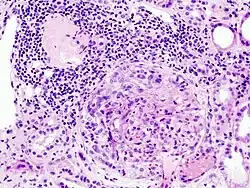

| Histopathological image of crescentic glomerulonephritis in a patient with MPO-ANCA positive rapid progressive glomerulonephritis. Hematoxylin & eosin stain. | |

Rapidly progressive glomerulonephritis (RPGN) is a syndrome of the kidney that is characterized by a rapid loss of kidney function,[4][5] (usually a 50% decline in the glomerular filtration rate (GFR) within 3 months)[5] with glomerular crescent formation seen in at least 50%[5] or 75%[4] of glomeruli seen on kidney biopsies. If left untreated, it rapidly progresses into acute kidney failure[6] and death within months. In 50% of cases, RPGN is associated with an underlying disease such as Goodpasture syndrome, systemic lupus erythematosus or granulomatosis with polyangiitis; the remaining cases are idiopathic. Regardless of the underlying cause, RPGN involves severe injury to the kidneys' glomeruli, with many of the glomeruli containing characteristic glomerular crescents (crescent-shaped scars).[7]